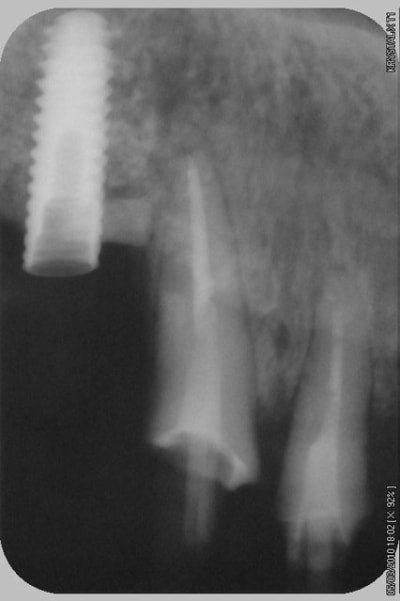

pour illustrer cette utilisation du bioactys, voici un cas (ce matin, mise en focntion des implants à 7 mois post_op)

C'était un peu limite non pour la pose immédiate, faible hauteur osseuse initiale.

pour la pose immédiate, çà dépend aussi du type d'implant utilisé...ici c'est des superline dentium...;-)

ils ont vraiment une super stab primaire, et leur design est parfait pour les zones sous sinusienne...entre autre....parce que pour l'instant, mis à part le manque d'un repère visible sur le préhenseur de la position de l'hex antirotationnel, j'ai pas encore trouvé de défaut au système...

ici c'est un mix (pour un impératif perso): en 25 un easy-implant master s puis 2 dentium superline.

Le easy c'est du sablé au corindon et les dentium sablés-mordancés SLA http://www.dentogem.com/viewpage.php?pageid=48

j'ai donc procédé à la mise en fonction ce matin, 7 mois après l'intervention. Mise en place de piliers de cicatrisation assez hautes et surtout de diamètres en adéquation avec une PM et 2M. je prends l'empreinte dans 3 semaines , la gencive sera belle autour des piliers.